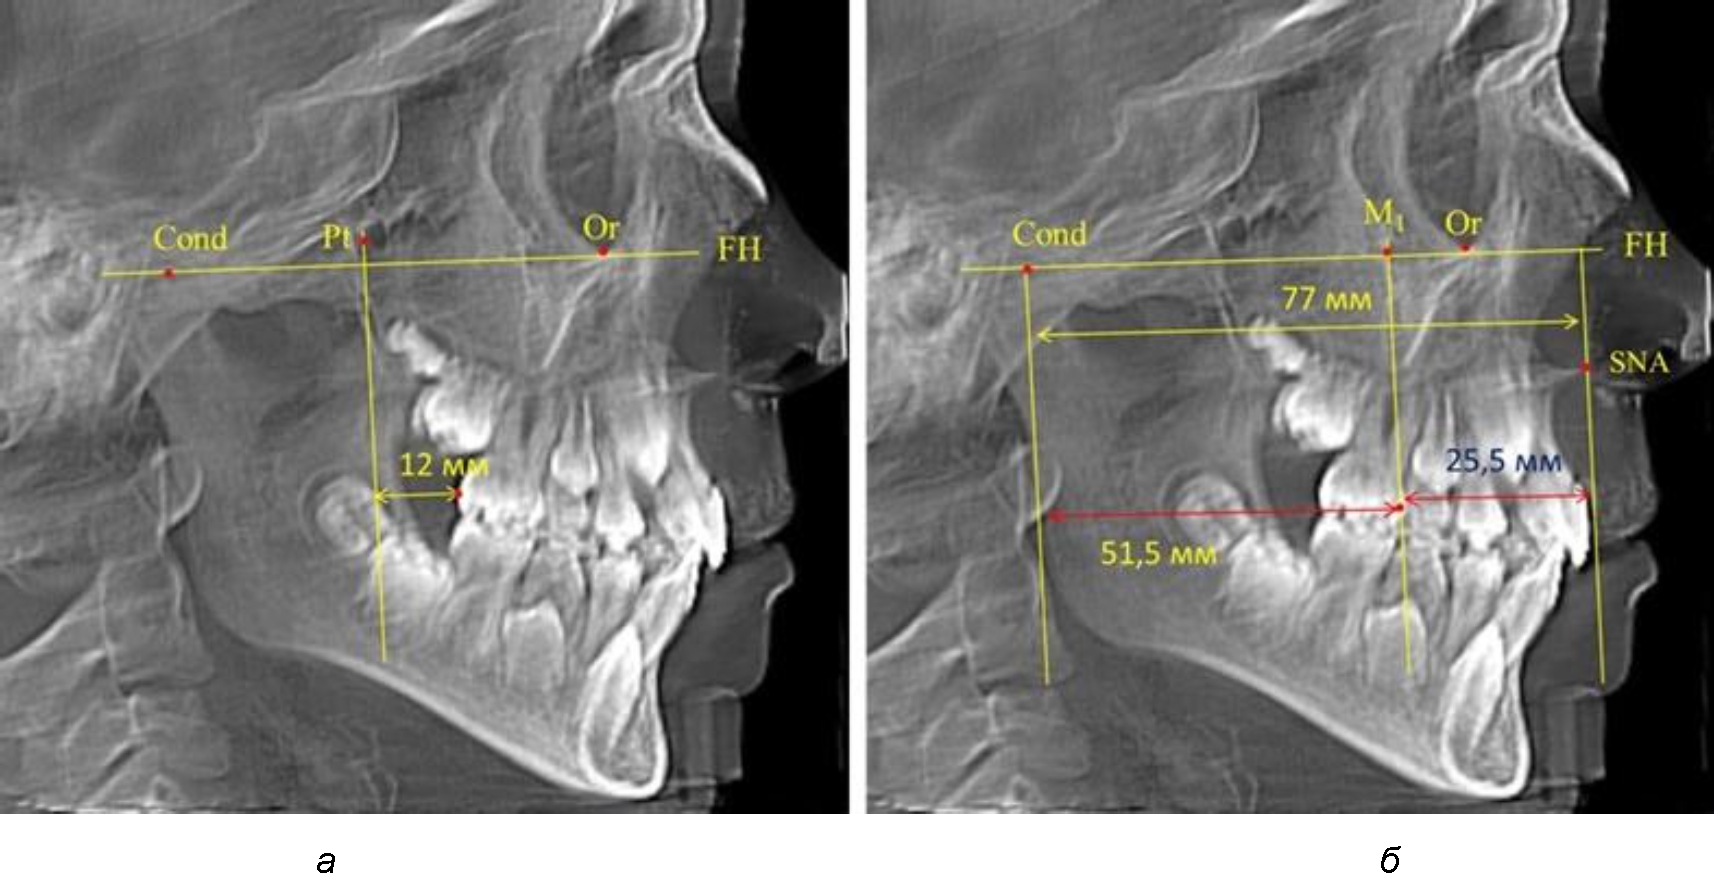

При проведении анализа к Франкфуртской горизонтали проводили передний и задний перпендикуляры. Передний спинальный перпендикуляр проходил через выступающую точку передней носовой ости (spina nasalis anterior – SNA), а задний суставной перпендикуляр опускали из кондилярной точки Cond. Молярный перпендикуляр проводили через медиальную поверхность первого постоянного моляра. Указанная вертикаль отделяла замещающие зубы постоянного прикуса от добавочных зубов (постоянных моляров), что вполне логично для анализа положения первых постоянных моляров в гнатическом комплексе (рис. 1).

Рис. 1. Метод определения положения первых верхних моляров по Ralph E. McDonald (а) и по предложенному методу (б)

Среди анализируемых рентгенограмм минимальное значение расстояния по методу R. E. McDonald было 12 мм, а максимальное достигало 25 мм, что, по нашему мнению, обусловлено вариабельностью сагиттального размера гнатического отдела лица.

Так, при расстоянии от крыловидной вертикальной плоскости PTV до дистальной поверхности верхнего первого постоянного моляра в 13 мм сагиттальный размер гнатического отдела был 82 мм. При этом отношение кондилярно-спинального расстояния к кондилярно-молярному размеру (54,5) было близким к коэффициенту 1,5, что представлено на рис. 2.

Рис. 2. Особенности положения первых моляров по R. E. McDonald (а) и по предложенному методу (б) при уменьшенном молярно-крыловидном расстоянии